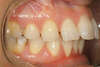

Décalage traité par gouttières

Fin de traitement